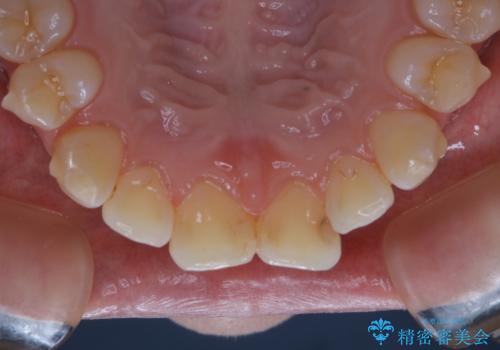

インビザラインでの治療中の患者様のクリーニング前後写真です。

- インビザライン矯正中に茶色が気になるとのことで来院されました。PMTC30分コースを行いました。